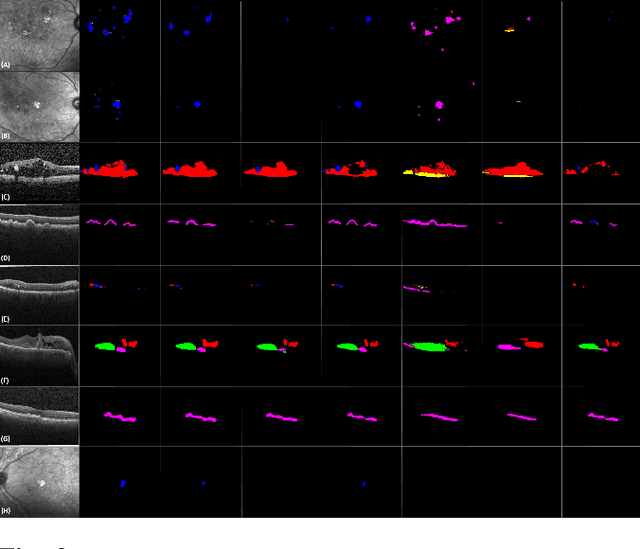

Abstract:Identification of lesions plays a vital role in the accurate classification of retinal diseases and in helping clinicians analyzing the disease severity. In this paper, we present a detailed evaluation of RAGNet, PSPNet, SegNet, UNet, FCN-8 and FCN-32 for the extraction of retinal lesions such as intra-retinal fluid, sub-retinal fluid, hard exudates, drusen, and other chorioretinal anomalies from retinal fundus and OCT scans. We also discuss the transferability of these models for extracting retinal lesions by varying training-testing dataset pairs. A total of 363 fundus and 173,915 OCT scans were considered in this evaluation from seven publicly available datasets from which 297 fundus and 59,593 OCT scans were used for testing purposes. Overall, the best performance is achieved by RAGNet with a mean dice coefficient ($\mathrm{D_C}$) score of 0.822 for extracting retinal lesions. The second-best performance is achieved by PSPNet (mean $\mathrm{D_C}$: 0.785) using ResNet\textsubscript{50} as a backbone. Moreover, the best performance for extracting drusen is achieved by UNet ($\mathrm{D_C}$: 0.864). The source code is available at: http://biomisa.org/index.php/downloads/.